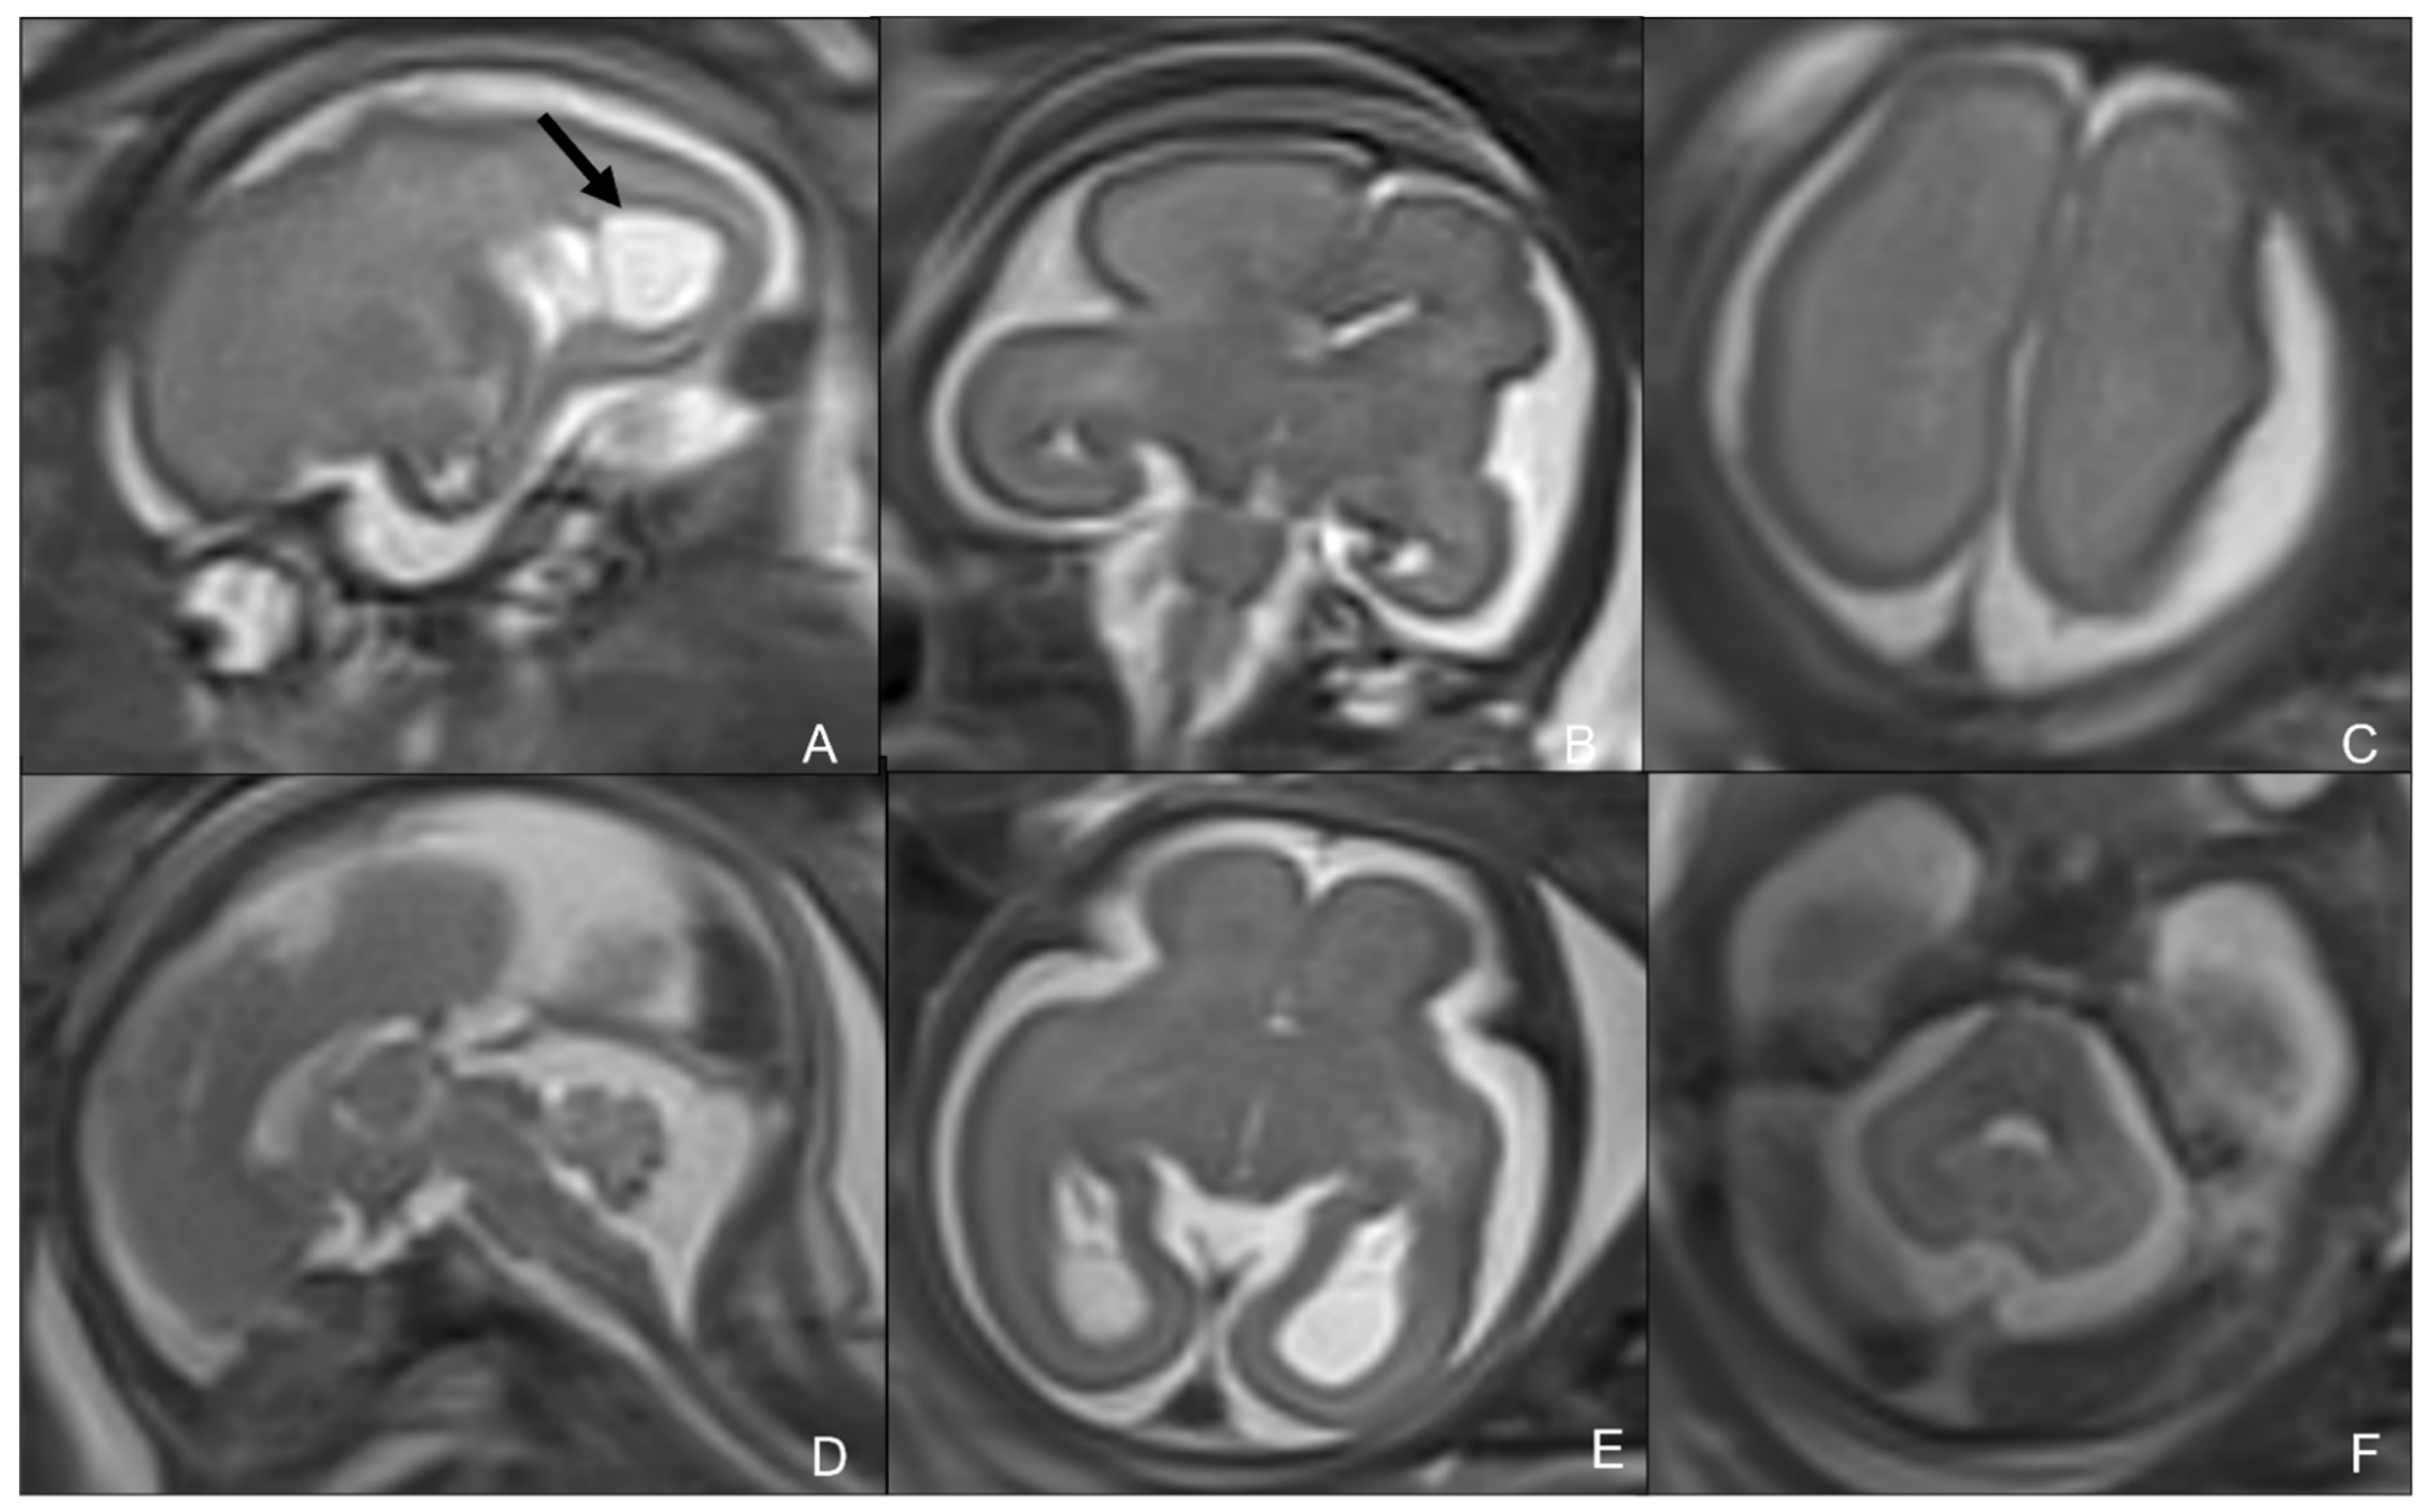

2.1. Cytomegalovirus Infection

- Diogo, M.C.; Glatter, S.; Binder, J.; Kiss, H.; Prayer, D. The MRI spectrum of congenital cytomegalovirus infection. Prenat. Diagn. 2020, 40, 110–124. [Google Scholar] [CrossRef]

- Barkovich, A.J.; Lindan, C.E. Congenital cyomegalovirus infection of the brain: Imaging analysis and embryologic considerations. AJNR Am. J. Neuroradiol. 1994, 15, 703–715. [Google Scholar] [PubMed]

- Averill, L.W.; Kandula, V.V.; Akyol, Y.; Epelman, M. Fetal Brain Magnetic Resonance Imaging Findings In Congenital Cytomegalovirus Infection with Postnatal Imaging Correlation. Semin. Ultrasound CT MRI 2015, 36, 476–486. [Google Scholar] [CrossRef]